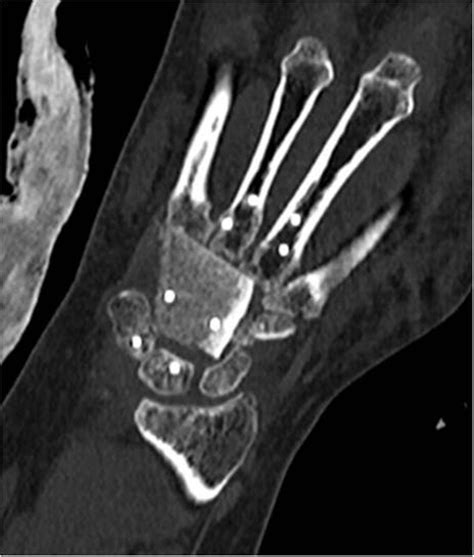

When you experience persistent pain, limited range of motion, or swelling following a fall or chronic strain, a radiograph of wrist is often the first diagnostic step your healthcare provider will recommend. This essential medical imaging tool provides a clear, high-contrast look at the intricate bone structure of your wrist, allowing clinicians to identify fractures, dislocations, or degenerative changes that might be causing your discomfort. Because the wrist is composed of eight small carpal bones alongside the distal ends of the radius and ulna, even minor misalignments can lead to significant functional impairment. Understanding what this procedure entails and what the resulting images can reveal is key to navigating your path toward recovery.

A radiograph, commonly known as an X-ray, uses a small, safe dose of ionizing radiation to create images of the internal structures of the body. When you arrive for your appointment, a radiologic technologist will guide you through positioning your hand and forearm on the imaging plate. The goal is to obtain clear views from multiple angles, which is critical because some hairline fractures may not be visible in a single dimension.

• Posteroanterior (PA) view: The palm is placed flat against the image detector. This provides the best overview of the carpal bones and the relationship between the radius and ulna.

• Lateral view: The hand is turned on its side. This view is essential for assessing the alignment of the lunate bone and checking for any anterior or posterior displacement of fragments.

• Oblique view: The wrist is rotated at a 45-degree angle. This helps in "unstacking" the bones that might overlap in the PA view, revealing potential occult fractures in the scaphoid or other carpal bones.

The primary utility of a radiograph of wrist is to rule out or confirm structural damage. Because of the complex anatomy of the carpal tunnel and the surrounding ligaments, identifying bone health is the foundational step for any treatment plan. Below is a breakdown of common findings documented in a radiograph report:

Once the radiograph of wrist is completed, a radiologist analyzes the images and provides a formal report. It is important to remember that a "normal" result does not always mean there is no injury. Soft tissue structures, such as the triangular fibrocartilage complex (TFCC) or various ligaments, do not show up on standard X-rays. If you have severe symptoms but the X-ray appears clear, your doctor may suggest advanced imaging like an MRI or CT scan to investigate ligaments and tendons further.